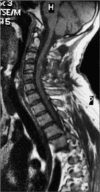

Background: Nonmissile penetrating spine injury (NMPSI) represents a small percent of spinal cord injuries (SCIs), estimated at 0.8% in Western countries. Regarding the causes, an NMPSI injury caused by a screwdriver is rare. This study reports a case of a retained double-headed screwdriver in a 37-year-old man who sustained a stab injury to the back of the neck, leaving the patient with a C4 Brown-Sequard syndrome (BSS). We discuss the intricacies of the surgical management of such cases with a literature review.

Conclusion: Screwdriver stabs causing cervical SCIs are extremely rare. This is the first case from Iraq where the assault device is retained in situ at the time of presentation. Such cases should be managed immediately to carefully withdraw the object under direct vision and prevent further neurological deterioration.